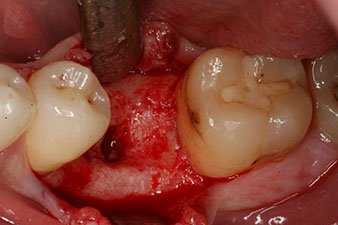

However, six weeks after the extraction incomplete ossification was found after preparation of the mucoperiosteal flap in the region of the former mesial alveolus.

The implant was placed as planned after thorough removal of the granulation tissue (blueSky, bredent).